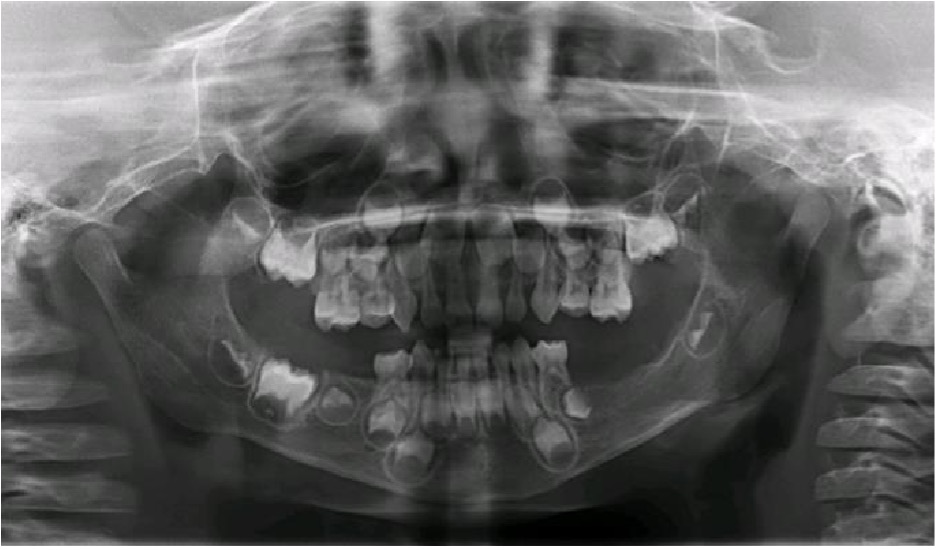

En el 2014, un dentista privado refirió a un paciente masculino de 3 años a la clínica de la Residencia de Odontopediatría de la Escuela de Medicina Dental de la Universidad de Puerto Rico, para evaluar una posible enfermedad periodontal en los segundos molares inferiores primarios1. El examen intraoral reveló una inflamación en la gingiva de los lados izquierdo y derecho, a nivel de los segundos molares inferiores primarios, obliterando el ángulo mandibular (Figura 1). Otros tejidos orales aparecieron dentro de los limites normales. En esa primera visita, luego del examen clínico, se obtuvo una radiografía panorámica la cual reveló una perdida ósea bilateral en los segundos molares primario derecho e izquierdo mandibular. La lesión del lado izquierdo mostraba un patrón radiolúcido extenso de márgenes irregulares desde el segundo molar primario hacia el folículo del primer molar permanente, desplazándolo posteriormente y creando una apariencia de dientes flotantes.1 El paciente recibió intervención quirúrgica con biopsia excisional y curetaje de las áreas afectadas con extracción de los segundos molares mandibulares primarios y el folículo del primer molar mandibular permanente izquierdo. Los especímenes obtenidos tanto del lado derecho como izquierdo mandibular fueron consistentes con Histiocitosis de Células de Langerhans. Posterior a este diagnóstico, el paciente fue referido al servicio de hematología/oncología para evaluación y tratamiento. Una tomografía computarizada fue ordenada la cual reveló que también había lesiones menores en el hígado y el área abdominal. El paciente fue tratado posteriormente con quimioterapia. Durante 3 años, el paciente continuó un protocolo riguroso de seguimientos dentales cada 3 meses con un dentista pediátrico y cada 6 meses con una cirujana maxilofacial. En el 2017, el seguimiento reveló en la radiografía panorámica y radiografía de mordida, una radio lucidez periapical del primer molar primario izquierdo envolviendo el primer premolar permanente. Debido al historial previo se tomó la decisión de realizar una segunda intervención en sala de operaciones donde se extrajeron el primer molar primario izquierdo y el folículo del primer premolar permanente izquierdo. El resultado de esa biopsia reveló un folículo dental agrandado y células inflamatorias sin evidencia de recurrencia de la lesión previa. En seguimiento, el paciente ha presentado exámenes clínicos y radiográficos periódicos sin evidencia de lesiones recurrentes. En el último seguimiento en el 2019, no reveló nuevas lesiones y el paciente se encontraba asintomático. La Figura 2, resume la toma de radiografías panorámicas durante el periodo de 2014 a 2019.

Radiografía panorámica (2015). Radiografía de seguimiento a los 3 meses postquirúrgicos mostrando un sanado óseo apropiado con continuidad mandibular sin evidencia de lesiones recurrentes.

Radiografía panorámica (2016). Radiografía de seguimiento con estabilidad y continuidad ósea del cuerpo mandibular izquierdo sin evidencia de recurrencia de lesiones

Figura 2. Serie de radiografías.